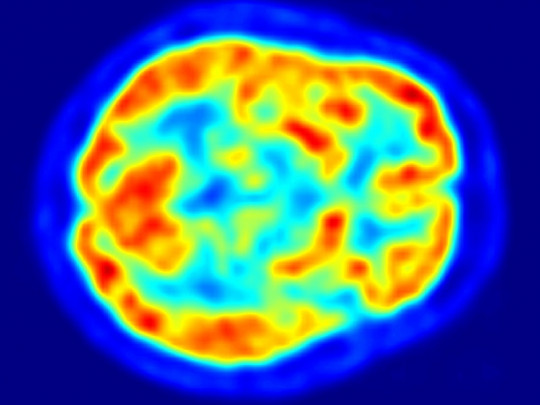

Está constituido por materia gris, es decir, por cuerpos de neuronas, dendritas amielínicas y células gliales. Se sitúa debajo de los hemisferios cerebrales, en la base del telencéfalo y en la parte central del encéfalo. Su forma es aproximadamente circular.